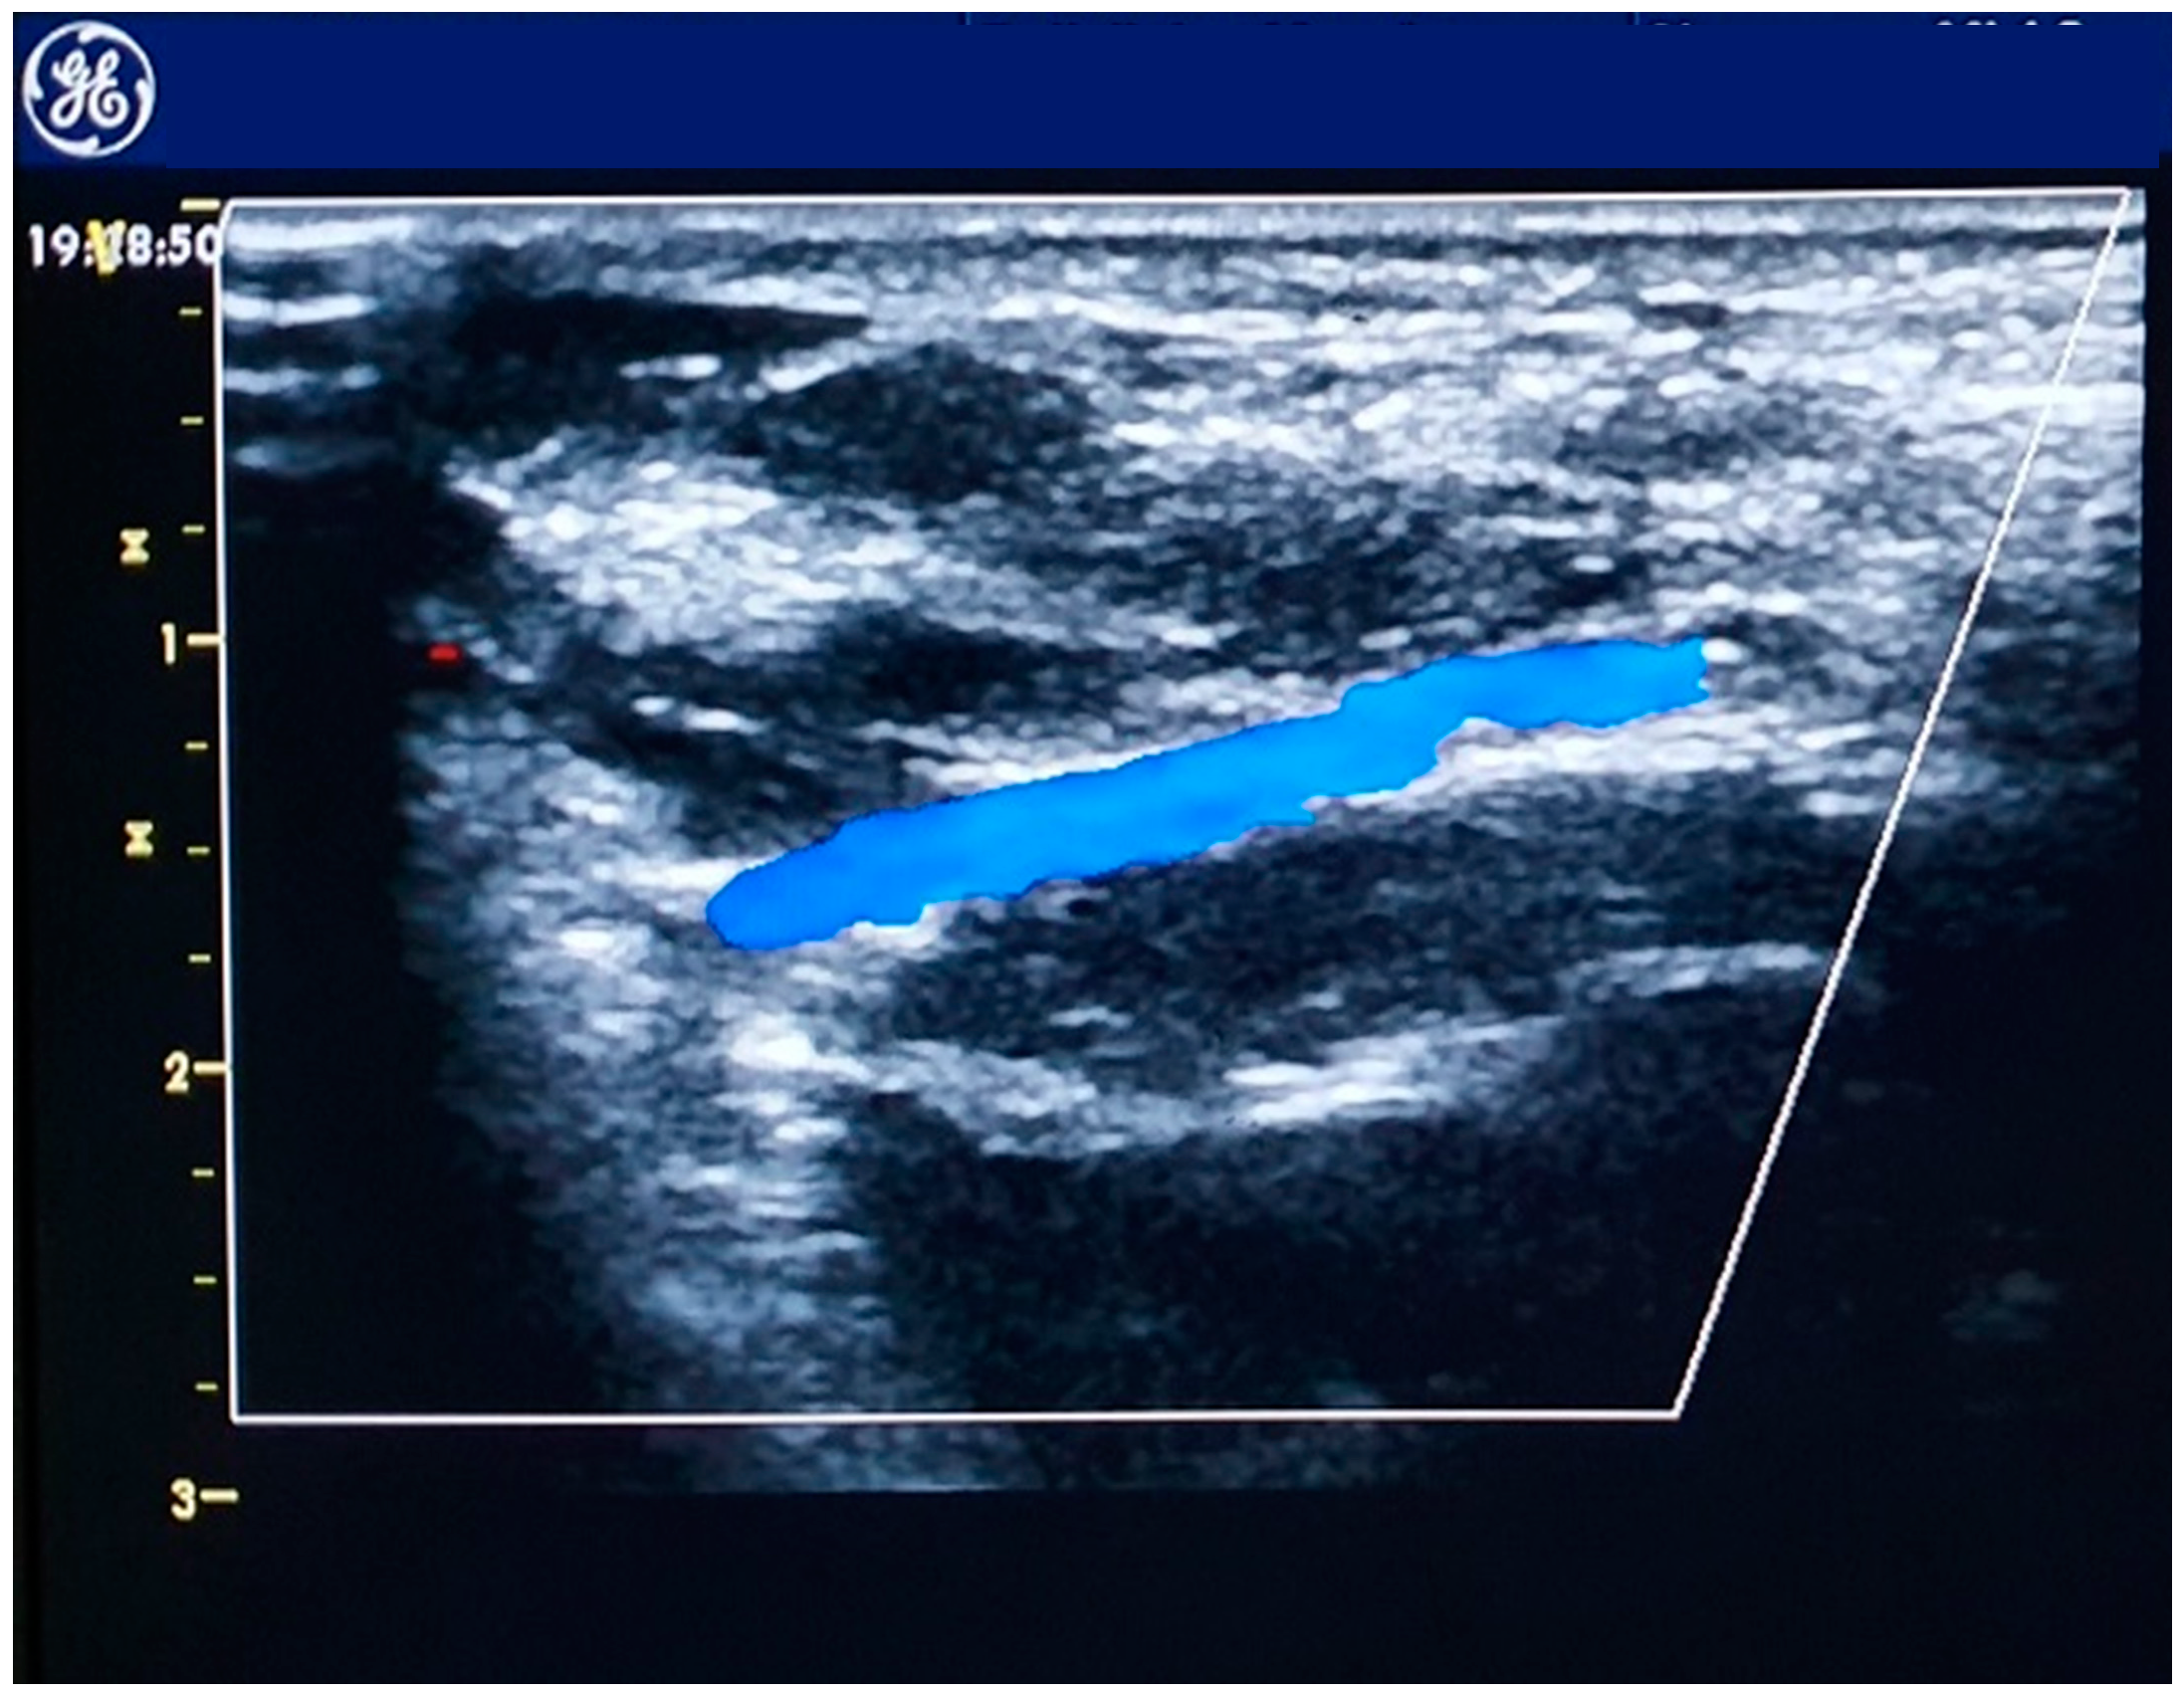

- Costa, F.; van Leeuwen, M.A.H.; Daemen, J.; Diletti, R.; Kauer, F.; van Geuns, R.-J.; Ligthart, J.; Witberg, K.; Zijlstra, F.; Valgimigli, M.; et al. The Rotterdam Radial Access Research: Ultrasound-Based Radial Artery Evaluation for Diagnostic and Therapeutic Coronary Procedures. Circ. Cardiovasc. Interv. 2016, 9. [Google Scholar] [CrossRef] [PubMed]

- Seto, A.H.; Roberts, J.S.; Abu-Fadel, M.S.; Czak, S.J.; Latif, F.; Jain, S.P.; Raza, J.A.; Mangla, A.; Panagopoulos, G.; Patel, P.M.; et al. Real-Time Ultrasound Guidance Facilitates Transradial Access. JACC Cardiovasc. Interv. 2015, 8, 283–291. [Google Scholar] [CrossRef] [PubMed]